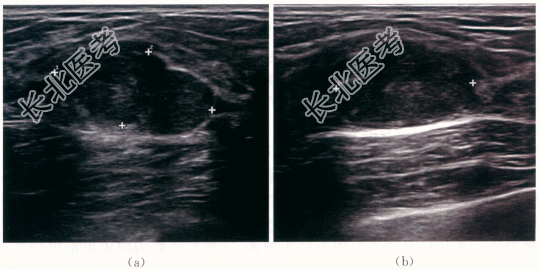

患者,女性,23岁,因“发现右乳肿块2周”就诊。患者于2周前无明显诱因下扪及右侧乳腺肿块,无明显压痛,无乳头溢液、溢血。患者平素月经规律,否认乳腺肿瘤家族史,否认妇科肿瘤病史。

患者右乳扪及多个结节,大小约黄豆至蚕豆大小,活动度好,表面光滑,局部皮肤未见明显改变。双乳未见明显凹陷。双侧腋窝未扪及明显肿大淋巴结。

右乳纤维腺瘤。